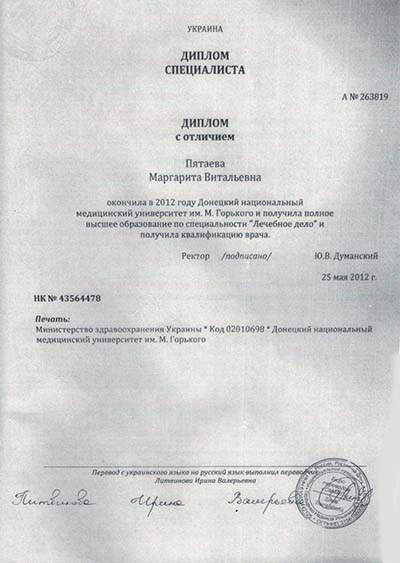

Лицензии и сертификаты

Лечение в нашей клинике анонимно, поэтому никто не узнает, что вы проходите или проходили лечение в нашем наркологическом центре.

Лицензии и сертификаты нашей клиники

Медицинские услуги оказываются ООО "ЮгЭкоСервис+" по лицензии ЛО-61-01-008143 от 28.12.2021 г.